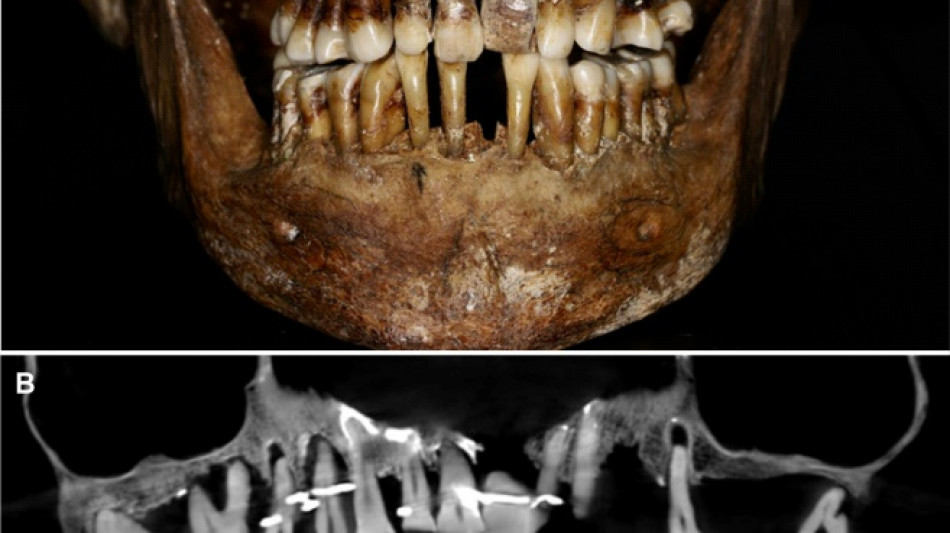

Embalmed in a lead coffin, her skeleton -- and teeth -- were remarkably well preserved.

Thirty-five years later, a team of archaeologists and dentists have identified that d'Alegre suffered from periodontal disease that was loosening her teeth, according to a study published in the Journal of Archaeological Science: Reports this week.

A "Cone Beam" scan, which uses X-rays to build three-dimensional images, showed that gold wire had been used to hold together and tighten several of her teeth.

She also had an artificial tooth made of ivory from an elephant -- not hippopotamus, which was popular at the time.